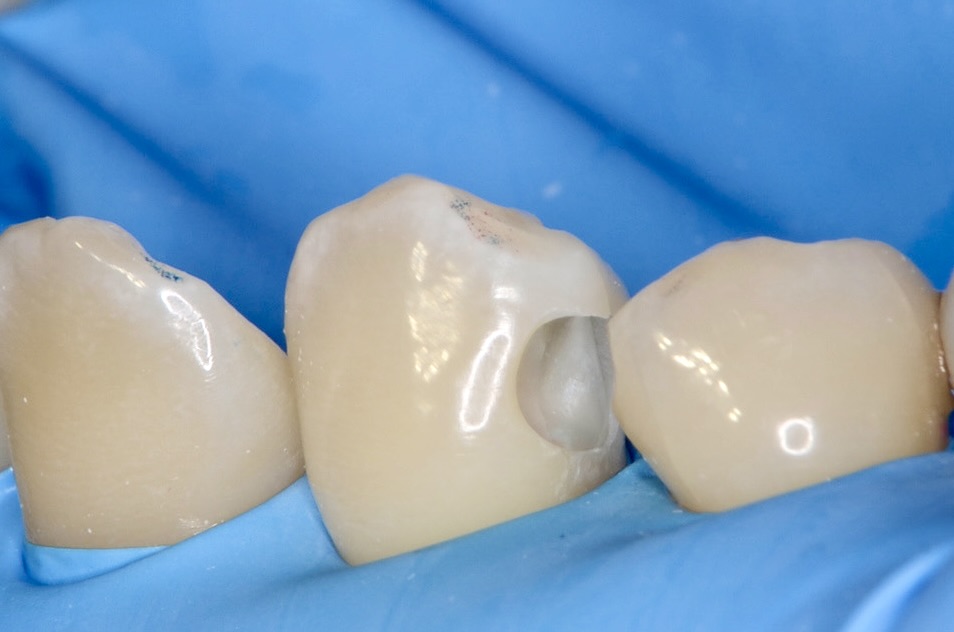

ホリゾンタルスロット

3番の健康な歯の部分を削る量をできるだけ少なくしたいので、歯の横からトンネルのように削っていきます。 -